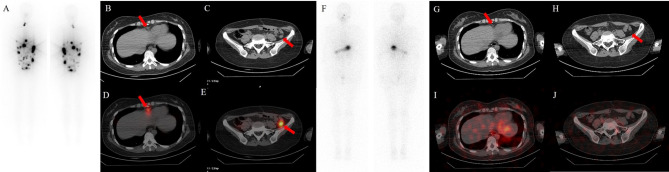

Case presentation: A 41-year-old Chinese woman underwent transabdominal left oophorectomy for a benign SO 18 years prior to presentation in the clinic. She was admitted to our institution for periodic medical examination after ultrasonography revealed a left pelvic mass. The patient underwent total abdominal hysterectomy, right salpingo-oophorectomy, and omentectomy, and multiple biopsies were taken from the omentum and mesentery. Pathology revealed peritoneal strumosis without evidence of malignancy from SO. Afterward, a total thyroidectomy was performed, and a histological examination revealed multinodular goiter. In total, 4400 MBq of 131I was administered, and lesion remission was confirmed. Finally, after 1 year of follow-up, the patient had no evidence of recurrence.